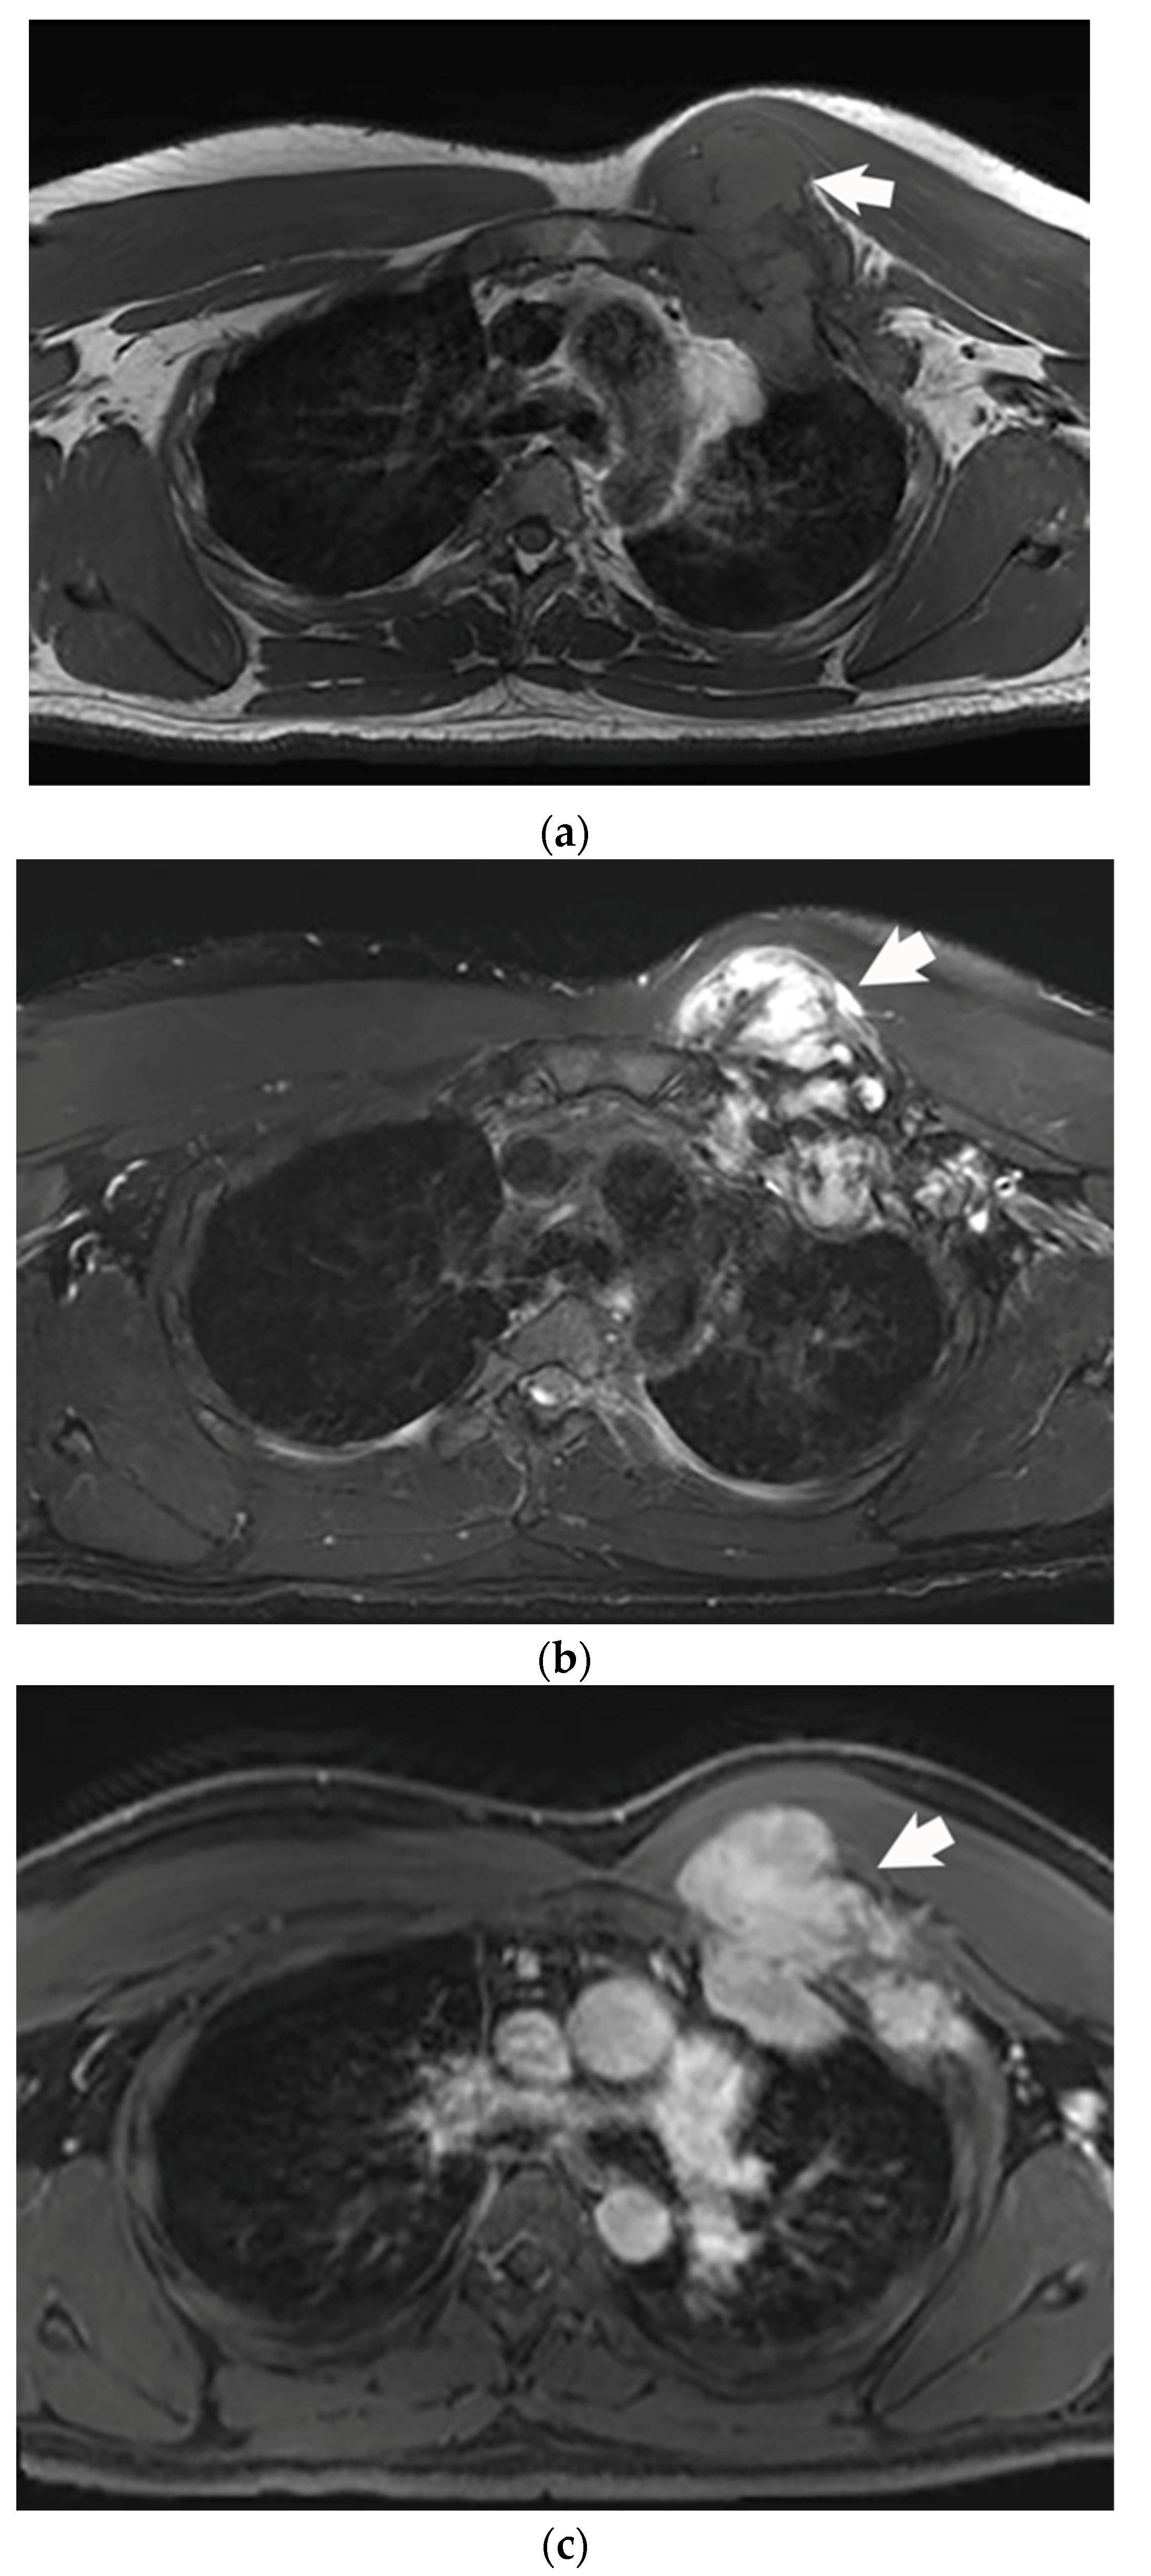

2. Imaging Characteristics